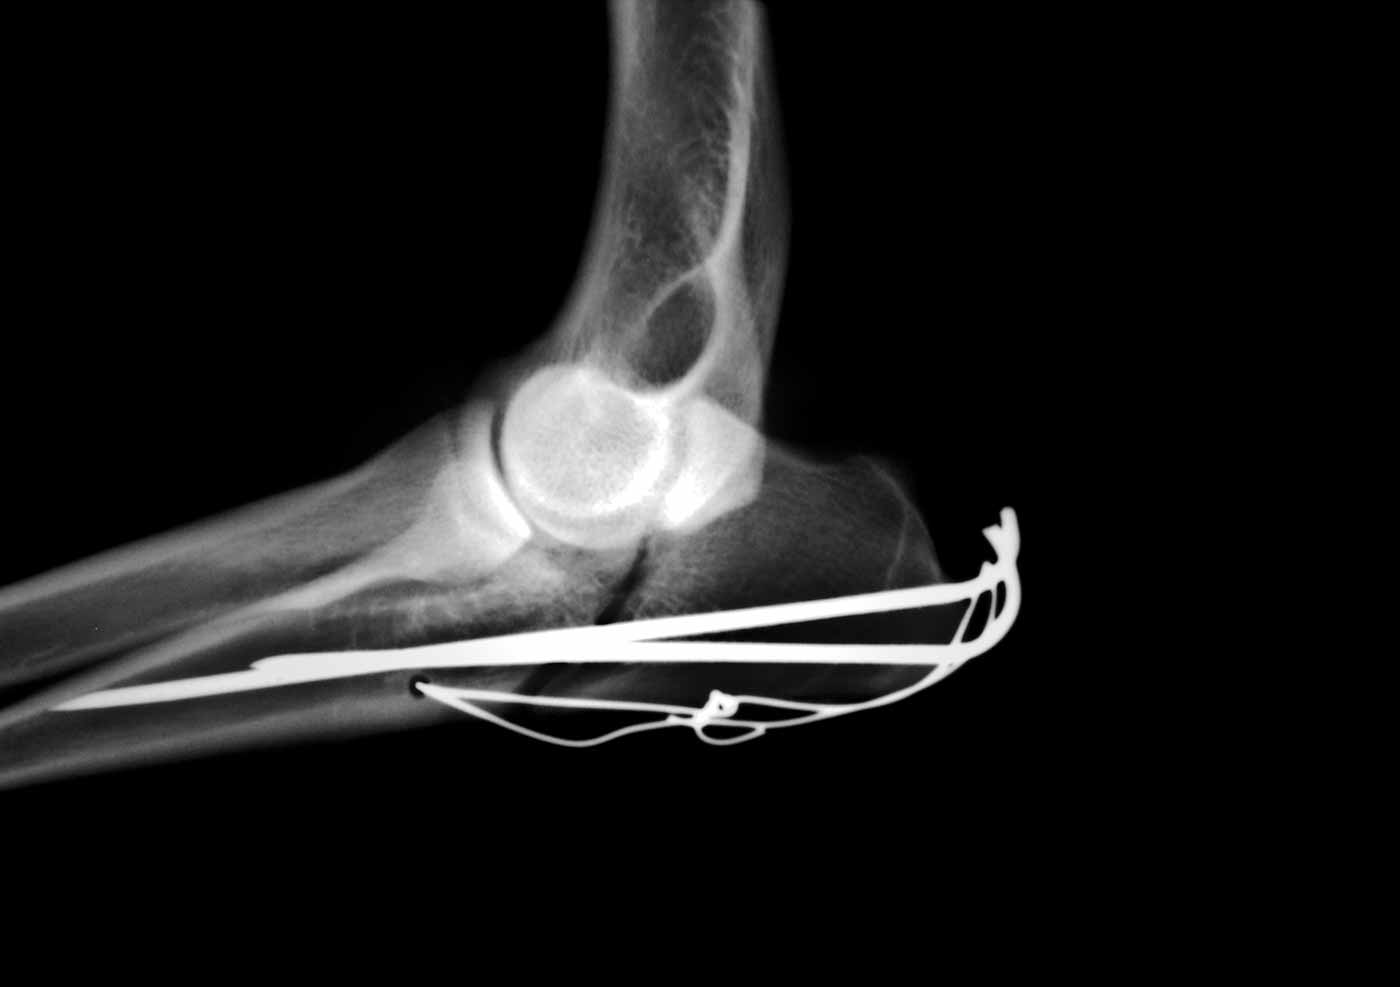

Digital Radiography

This advanced digital technology allows us to take quicker and clearer x-ray images that give us a more detailed picture of what is happening in your pet. Doctors can alter the radiograph to get a closer look than they can with film technology.